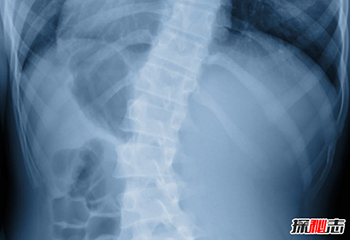

X射线应用于医学诊断,主要依据X射线的穿透作用、差别吸收、感光作用和荧光作用,也就是大家所“拍摄”的X光。

由于X射线穿过人体时,受到不同程度的吸收,如骨骼吸收的X射线量比肌肉吸收的量要多,那么通过人体后的X射线量就不一样,这样便携带了人体各部密度分布的信息,在荧光屏上或摄影胶片上引起的荧光作用或感光作用的强弱就有 较大差别,因而在荧光屏上或摄影胶片上将显示出不同密度的阴影。

根据阴影浓淡的对比,结合临床表现、化验结果和病理诊断,即可判断人体某一部分是否正常。

X射线的用途主要是探测骨骼的病变,但对于探测软组织的病变也相当有 用。

常见的例子有 胸腔X射线,用来诊断肺部疾病,如肺炎、肺癌或肺气肿;而腹腔X射线则用来检测肠道梗塞,自由气体及自由液体。